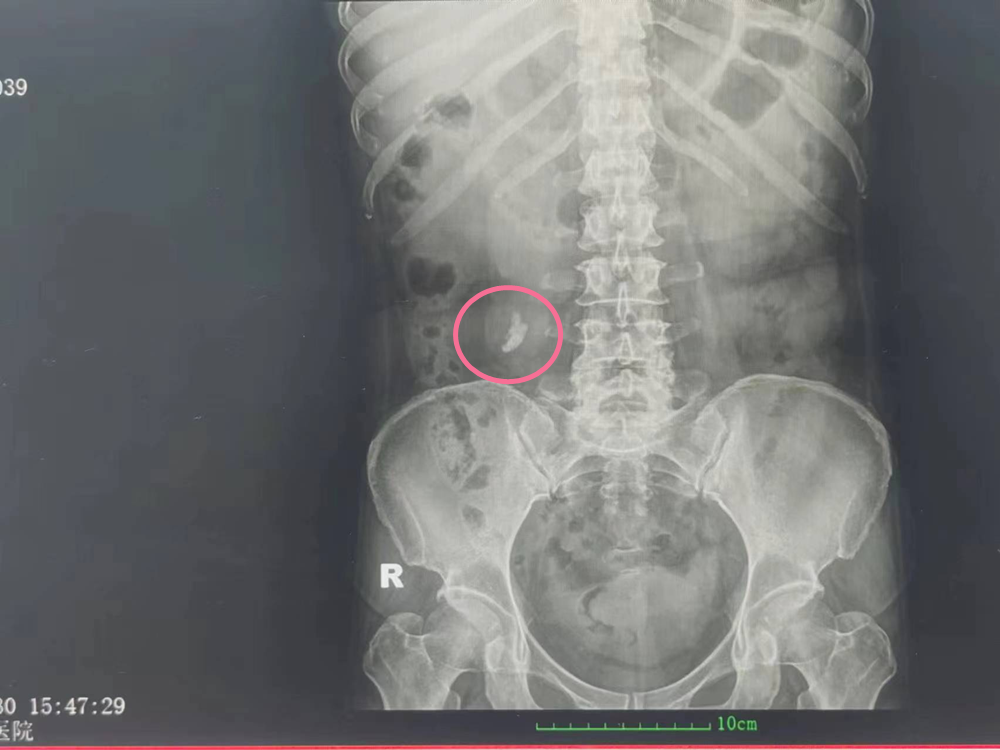

患者陈女士、45岁,以“反复右腰腹部疼痛伴血尿2天”之主诉入院。2天前患者无明显诱因出现右腰腹部疼痛不适,阵发性发作,时有尿痛、血尿等症状。

入院经进一步检查及病例分析后,因患者右输尿管上段结石并右肾重度积水,严重影响到了正常生活,我院泌尿外科主任严共全接手后,决定带领团队完善术前准备,为患者行右侧经皮肾镜碎石取石术+输尿管支架置入术。

患者术前右输尿管上段结石

术前右肾重度积水